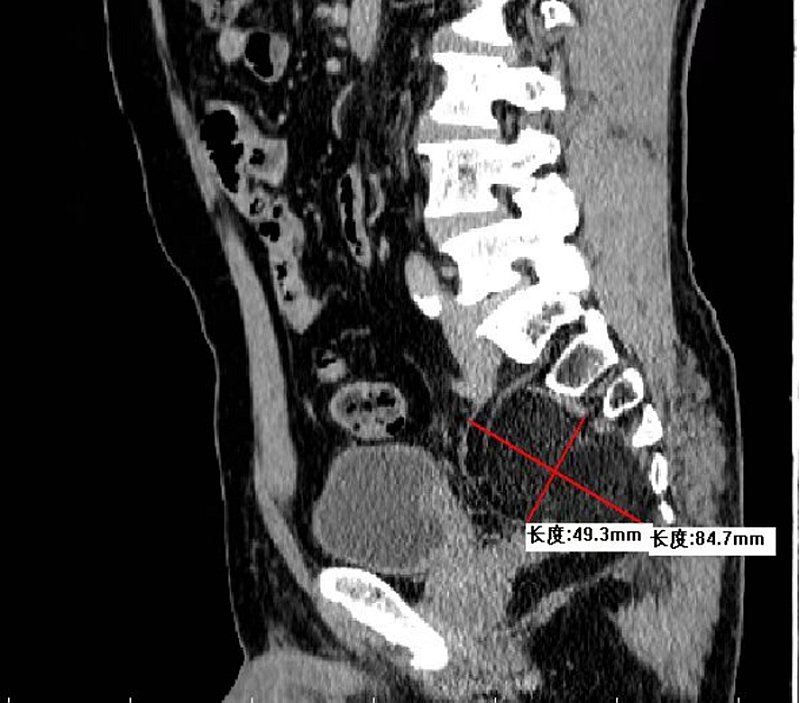

入院后检查发现,王先生盆腔内肿块范围约8.5cm×4.9cm,左侧髂内动静脉、坐骨神经从中穿行,肿块已压迫周围组织,导致其左下肢发麻。若不及时处理,可能引起下肢瘫痪甚至大血管破裂等严重后果。